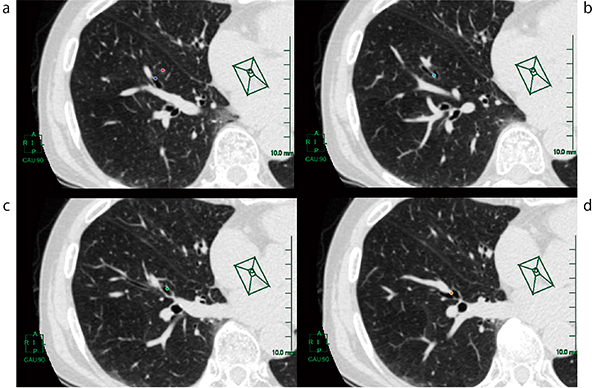

(1) AZE VirtualPlaceの仮想内視鏡画像作成用のアプリケーションにて,二次元画像上で目印を付けていく(図3)。右肺S8病変部(図3 a ●),病変部から垂直に下ろした気管支との交点(図3 a ●),そこから末梢の気管支分岐部(図3 b ●),1つ近位の気管支分岐部(図3 c ●),2つ近位の気管支分岐部(図3 d ●)とする。

図3 画像処理:目印の作成